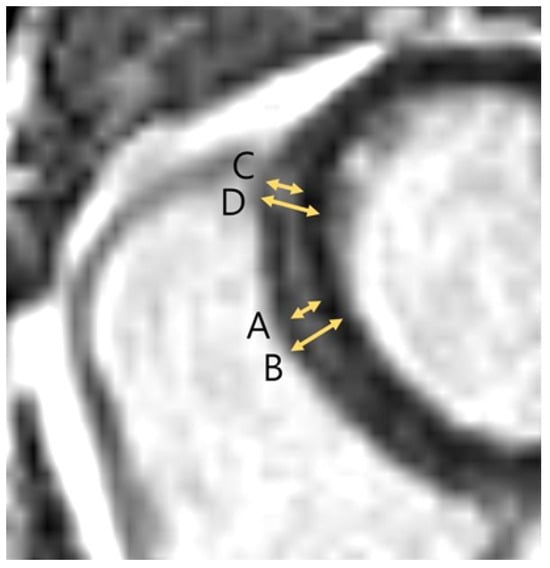

| Maximal thickness of upper RVIP LGE stripes | 6.1 ± 1.9 mm (n = 239) | 8.7 ± 2.7 mm (n = 80) | <0.001 |

| % thickness of upper RVIP basal LGE stripes | 42.2 ± 10.6% (n = 237) | 57.5 ± 13.0% (n = 79) | <0.001 |

| % thickness of upper RVIP middle LGE stripes | 44.3 ± 10.1% (n = 39) | 59.4 ± 15.8% (n = 14) | 0.005 |

| % thickness of upper RVIP LGE stripes | 42.5 ± 10.6% | 57.8 ± 13.4% | <0.001 |

| Maximal thickness of mid-septal LGE stripes | 4.5 ± 1.3 mm (n = 270) | 5.7 ± 1.8 mm (n = 100) | <0.001 |

| % thickness of mid-septal segment 1, 2 stripes | 37.0 ± 9.5% (n = 267) | 44.3 ± 10.4% (n = 99) | <0.001 |

| % thickness of mid-septal segment 3, 4 stripes | 29.5 ± 9.3% (n = 197) | 39.9 ± 9.9% (n = 77) | <0.001 |

| % thickness of mid-septal segment 8, 9 stripes | 32.9 ± 9.8% (n = 239) | 44.2 ± 12.2% (n = 87) | <0.001 |

| % thickness of mid-septal segment 14 stripes | 32.2 ± 7.9% (n = 117) | 42.6 ± 11.7% (n = 33) | <0.001 |

| % thickness of mid-septal stripes | 33.3 ± 9.8% | 42.9 ± 11.1% | <0.001 |

| Maximal thickness of lower RVIP LGE stripes | 6.4 ± 2.3 mm (n = 266) | 8.6 ± 2.8 mm (n = 99) | <0.001 |

| % thickness of lower RVIP basal LGE stripes | 49.4 ± 12.6% (n = 252) | 58.5 ± 12.3% (n = 95) | <0.001 |

| % thickness of lower RVIP middle LGE stripes | 47.1 ± 12.5% (n = 248) | 56.3 ± 13.0% (n = 86) | <0.001 |

| % thickness of lower RVIP LGE stripes | 48.2 ± 12.6% | 57.5 ± 12.6% | <0.001 |